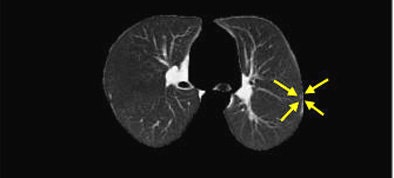

| Nodules detected by ROI detection system. Top, small nodule with inconspicuous intensity difference with surrounding lung context. Below, small well-formed nodule. Third from top, small nodule hardly distinguishable from the background and nearby thin vessels. Bottom, small irregularly shaped nodule. All images courtesy of Javad Alirezaie, Ph.D. |